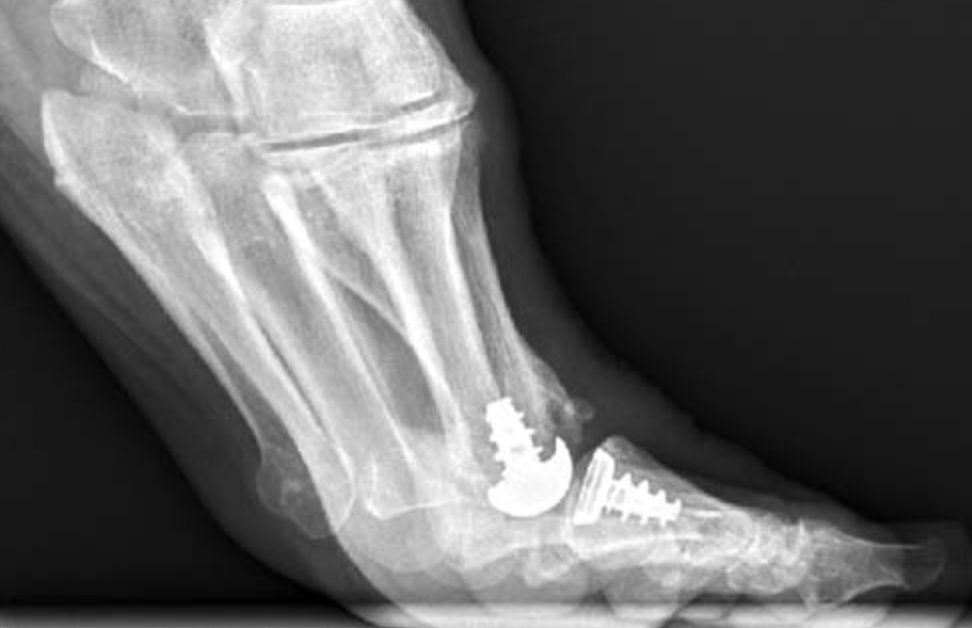

Joint replacement

Options

Hemiarthroplasty

Total joint arthroplasty

- silastic implants

- press fit metal / polyethylene

Anika Toe Motion Implant System

Total toe replacement

- 47 patients reviewed at mean of 10 years

- screw in metal Toe-Fit Plus implant

- 51% reported satisfactory results

- 23% ongoing pain

- 21% removal of implants

Clough et al Bone J Journal 2020

- 108 cases silastic joint replacement

- mean follow up 5 years

- 97% survival

- 90% satisfaction